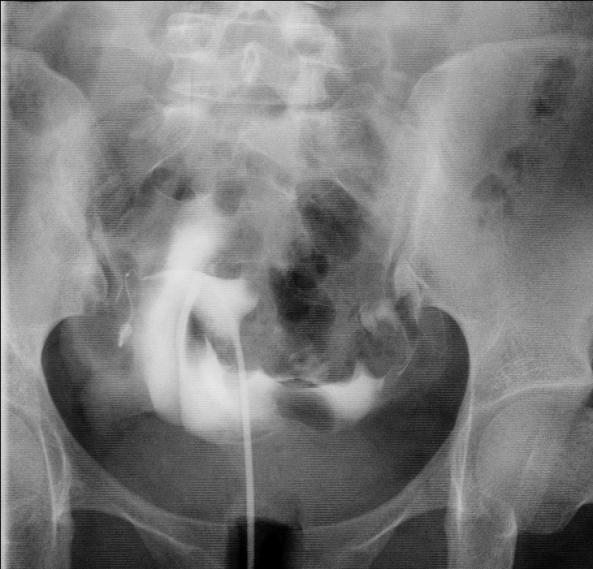

2019年2月27日,由于基层大夫跟我关系很好,把她介绍到我这里看看,来时就说“能看就看,如果花费太大,就不看了”,我就先让她做了一个无痛不插管子宫输卵管造影检查,结果显示:左侧输卵管通而不畅,右侧输卵管不通,通过片子,我觉得她的右侧输卵管已经没有希望,来的太晚了,剩下的左侧输卵管还不是完全通畅的,目前的情况是想花钱少又想怀孕,就好好听话,好好治疗,不然宫外孕就更惨了。

当日她经过激烈的家庭讨论,听说硬是咬牙跺脚从牙缝中挤出来的一万块钱,同意做输卵管介入疏通治疗,我也很感动,决定为他们亲自上手术,最后的治疗的结果是这样的:我觉得她如果能真正遵从医嘱,三个月到半年内应该能够顺利怀孕。